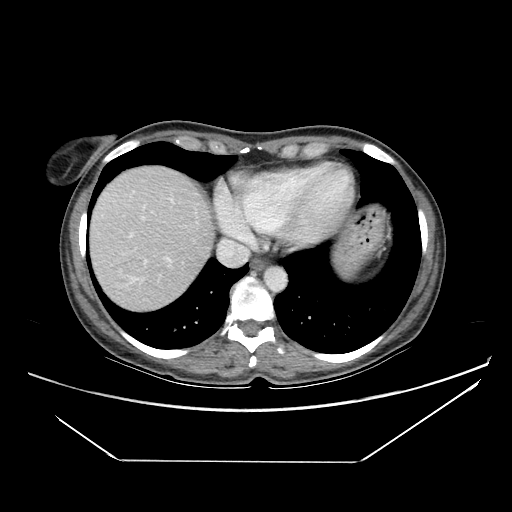

Image Grid

4Γ—3 grid: Rows show different image types (Original NATIVE, Reconstructed NATIVE, Original VENOUS, Generated VENOUS), Columns show windowing techniques (No Window, Lung Window, Mediastinum Window)

Original VENOUS CT scan

Full window (WL 1023.5, WW 4095 β†’ Low βˆ’1024, High +3071)

Mediastinum window (WL 40, WW 400 β†’ Low βˆ’160, High +240)